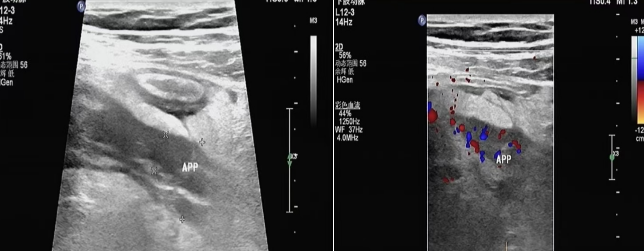

直接征象:管徑增粗(成人≥7mm,兒童≥6mm)、壁增厚 (>3mm)、周圍血流信號(hào)增多。

闌尾顯著腫脹,漿膜高度充血,被纖維蛋白與膿性滲出物覆蓋,或大網(wǎng)膜包裹,闌尾腔內(nèi)積膿,腔壁小膿腫形成。超聲圖:闌尾明顯增粗,外徑>10mm,闌尾壁明顯增厚,呈不均勻低回聲,各層次厚薄不一,壁內(nèi)彩色血流豐富。部分腔內(nèi)可見積液或絮狀沉積物或糞石。腹腔可見渾濁滲出液或膿液。